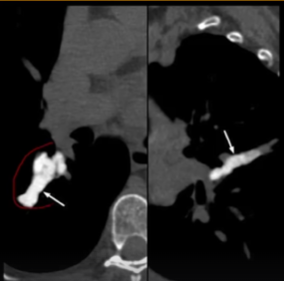

Sinais e padrões torácicos

SINAL DO HALO

Denifição

A

Opacidades em vidro fosco circundando um nódulo/massa

9

Q

10

Em que perfi de paciente pode apresentar esse padrão?

• Pacientes com neutropenia Febril

• Sugestivo de aspergilose angioinvasiva